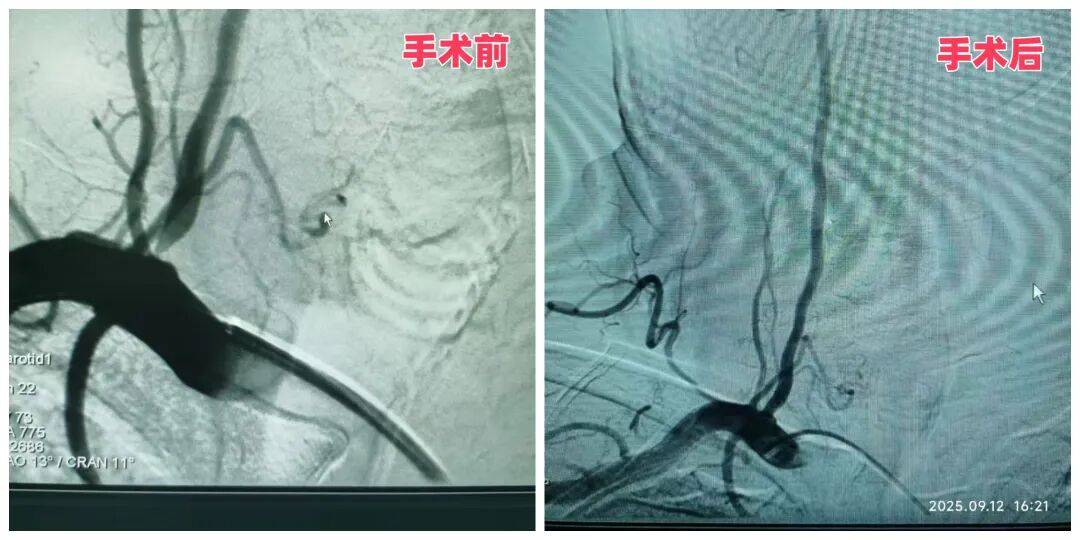

57歲的李大哥半年內(nèi)因反復(fù)頭暈住院三次,出現(xiàn)兩次右側(cè)小腦急性梗死,經(jīng)檢查確診為“雙側(cè)椎動(dòng)脈起始段狹窄”,其中右側(cè)已達(dá)重度狹窄,隨時(shí)可能再次引發(fā)腦梗。神經(jīng)內(nèi)科二病區(qū)主任袁秀琴、主管醫(yī)生楊偉偉、護(hù)士長馬曉玲結(jié)合患者的高血壓、糖尿病病史及既往腦梗情況,術(shù)前為患者進(jìn)行降壓、降糖治療,并制定了 “主動(dòng)脈弓 + 腦血管造影術(shù) + 右側(cè)椎動(dòng)脈支架植入” 的精準(zhǔn)治療方案。

手術(shù)中,醫(yī)生憑借豐富的介入經(jīng)驗(yàn),將支架精準(zhǔn)植入右側(cè)椎動(dòng)脈狹窄處,成功撐開狹窄血管。術(shù)后復(fù)查患者右椎動(dòng)脈供血恢復(fù)正常。這例手術(shù)的成功,標(biāo)志著科室在腦血管狹窄精準(zhǔn)治療領(lǐng)域的技術(shù)已趨于成熟,能為復(fù)雜病情患者提供安全有效的方案。